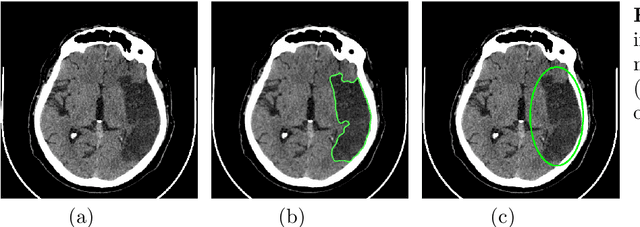

Abstract:This paper presents an automatic algorithm for the segmentation of areas affected by an acute stroke on the non-contrast computed tomography brain images. The proposed algorithm is designed for learning in a weakly supervised scenario when some images are labeled accurately, and some images are labeled inaccurately. Wrong labels appear as a result of inaccuracy made by a radiologist in the process of manual annotation of computed tomography images. We propose methods for solving the segmentation problem in the case of inaccurately labeled training data. We use the U-Net neural network architecture with several modifications. Experiments on real computed tomography scans show that the proposed methods increase the segmentation accuracy.